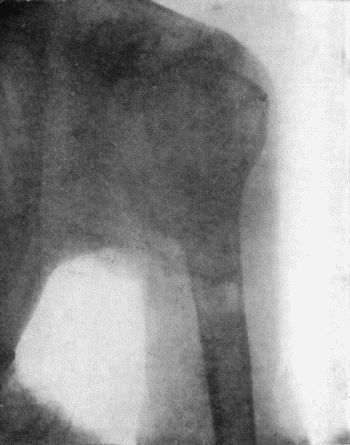

121.Radiogram of Brodie's Abscess in Lower End of Tibia 451

122.Sequestrum of Femur after Amputation 453